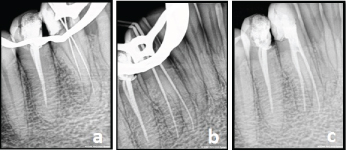

The caries on the disto-buccal surface was excavated and restored with composite resin (3M ESPE, A G Seefeld, Germany). Local anesthesia was administered and access opening was done using endo-access bur (Dentsply Tulsa, Tulsa, OK) under rubber dam isolation. The pulp chamber was opened to facilitate location of buccal and lingual canals. Working length was established using apex locator and also radiographically [Table/Fig-2a].

Working length. b) Master cone. c) Obturation.

The canals were instrumented using stainless steel K- files (Dentsply Maillefer, Ballaigues, Switzerland) with master apical filing upto #35 K-file. A 5.2% solution of sodium hypochlorite and 17% EDTA were used alternatively as irrigants, at each change of file. Final irrigation was done using 2% chlorhexidine [Table/Fig-2b]. The canals were dried with absorbent paper points (Dentsply, DeTrey, Konstanz, Germany). The instrumented root canals were obturated using 2% gutta percha cones and AH Plus sealer (Dentsply, DeTrey, Konstanz, Germany) using lateral condensation technique. The final radiograph showed two well-obturated canals. After completion of root canal treatment, the tooth was restored using resin composite (3M ESPE, A G Seefeld, Germany) [Table/Fig-2c].